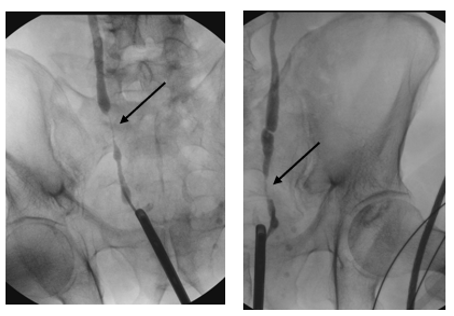

The patient underwent an elective diagnostic cystoscopy and TURBT. The diagnostic cystoscopy (see Figure 1) showed diffuse erythematous and edematous bladder mucosa without any distinct papillary or nodular suspicious lesions. Random cold biopsies and targeted warm biopsies of the erythematous regions were obtained. Retrograde ureteroscopy was not possible; therefore, a retrograde ureterography (see Figure 2) was performed, which showed bilateral distal ureteral stenosis approximately 3 cm proximal to the ureteric orifices, raising suspicion of external compression.

Figure 1: Diagnostic cystoscopy with erythematous and edematous bladder mucosa